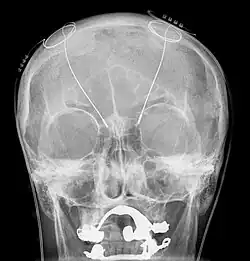

Basically it involves the implantation of electrodes into the brain. Usually they are positioned in the subthalamic nucleus but sometimes other targets can be used including the internal segment of the globus pallidus and the thalamus. Small electrical pulses are applied through these electrodes by means of a controller implanted under the skin of the chest or abdomen.